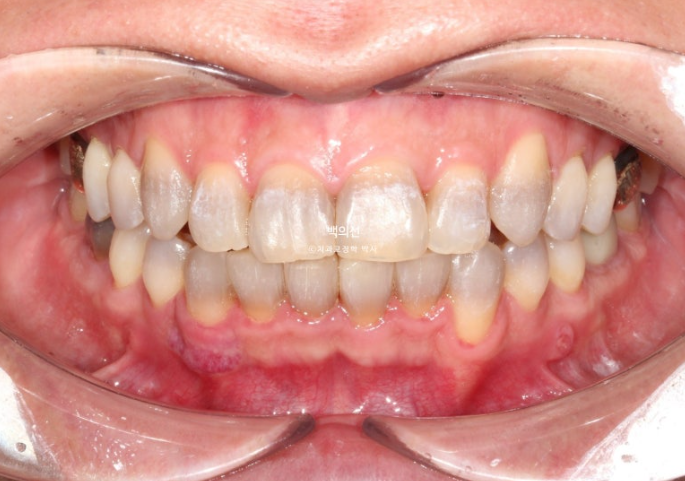

Now let’s compare the initial visit, after orthodontic treatment, and after Gelami in sequence.

23.12~25.06

This is an occlusal surface photo that gives an idea of the thickness of Gelami.

No-prep laminate has to be made thin, so the original tooth color inevitably shows through to some extent. In the facial photo, it can be seen that the original dark gray tooth color is showing through.

The way to prevent this gray tone from showing through is to remove some tooth structure and make the laminate thicker.

However, the patient wanted a no-prep approach, so we decided to accept some degree of gray tone.

The orthodontic result shows good root parallelism.